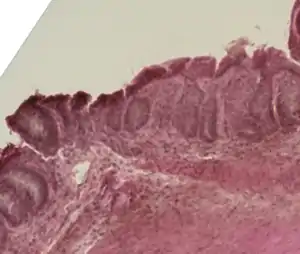

| Mouse colon impacted by acute graft-versus-host disease. | |